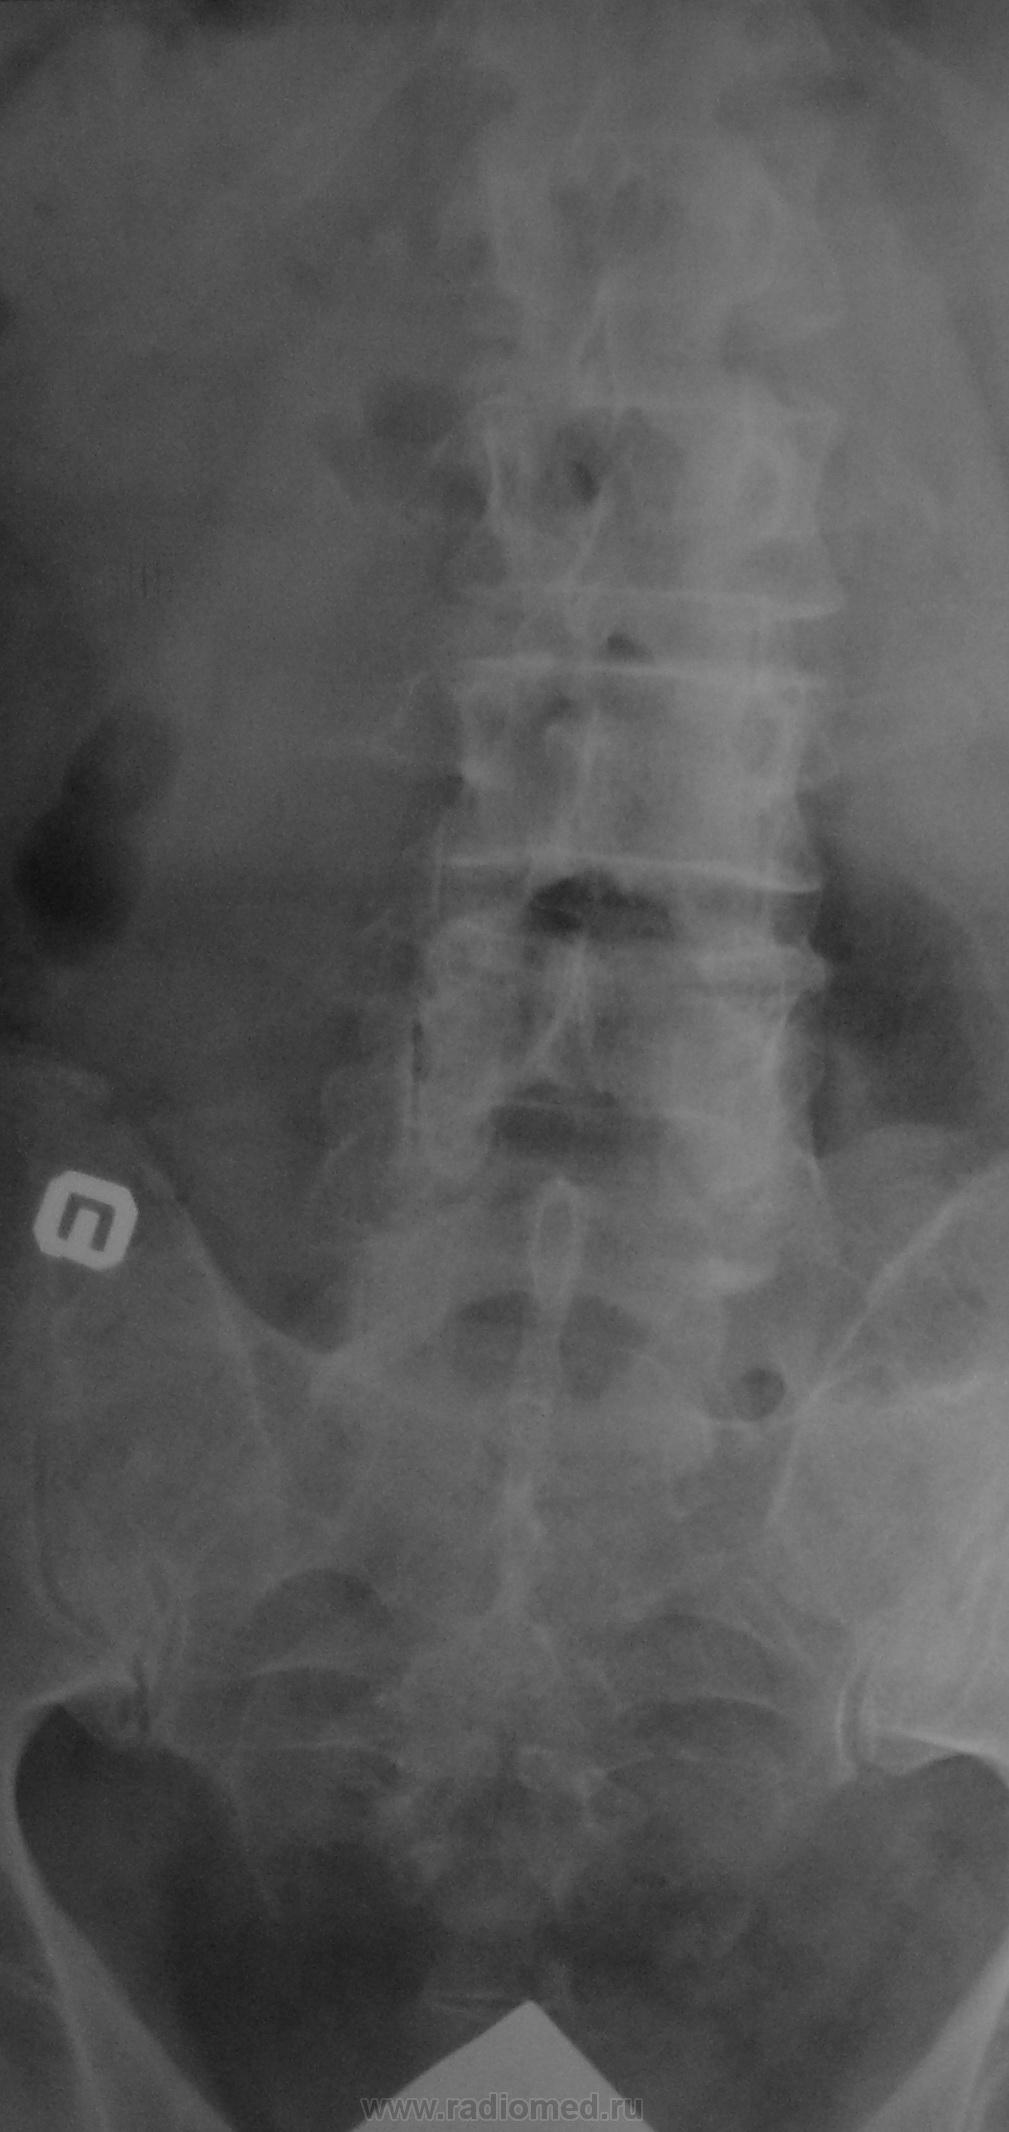

Случай №1 Беспокоят сильные боли в проекции L5 У меня сложилось впечатление, что там намечается спондилолиз. Мужчина. 50 лет

Случай №2 Здесь женщина, 60 лет. Болит в этой же проекции L5

Случай №1. Спондилолиз L5. Спондилолистез L4

Случай №2. Ложный спондилолистез L5.

В первом случае - антеспондилолистез L4, спондилолиза, если честно не вижу, было бы здорово стрелочку)

Во втором - тоже антеспондилолистез L4. Переходный пояснично-крестцовый позвонок?. Ну и спондилез, спондилоартроз, а также левосторонний сколиоз ПОП с ротацией позвонков.